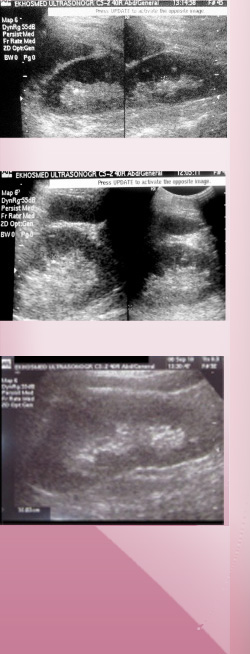

Examen que permite evaluar los riñones, en lo que respecta a su morfología y características estructurales, descarta patologías tumorales y presencia de litiasis o fenómenos obstructivos presentes en el sistema excretor renal, secundario a litiasis en la vía urinaria.

Se utiliza en controles de patología renal, evaluaciónde insuficiencia renal entre otras